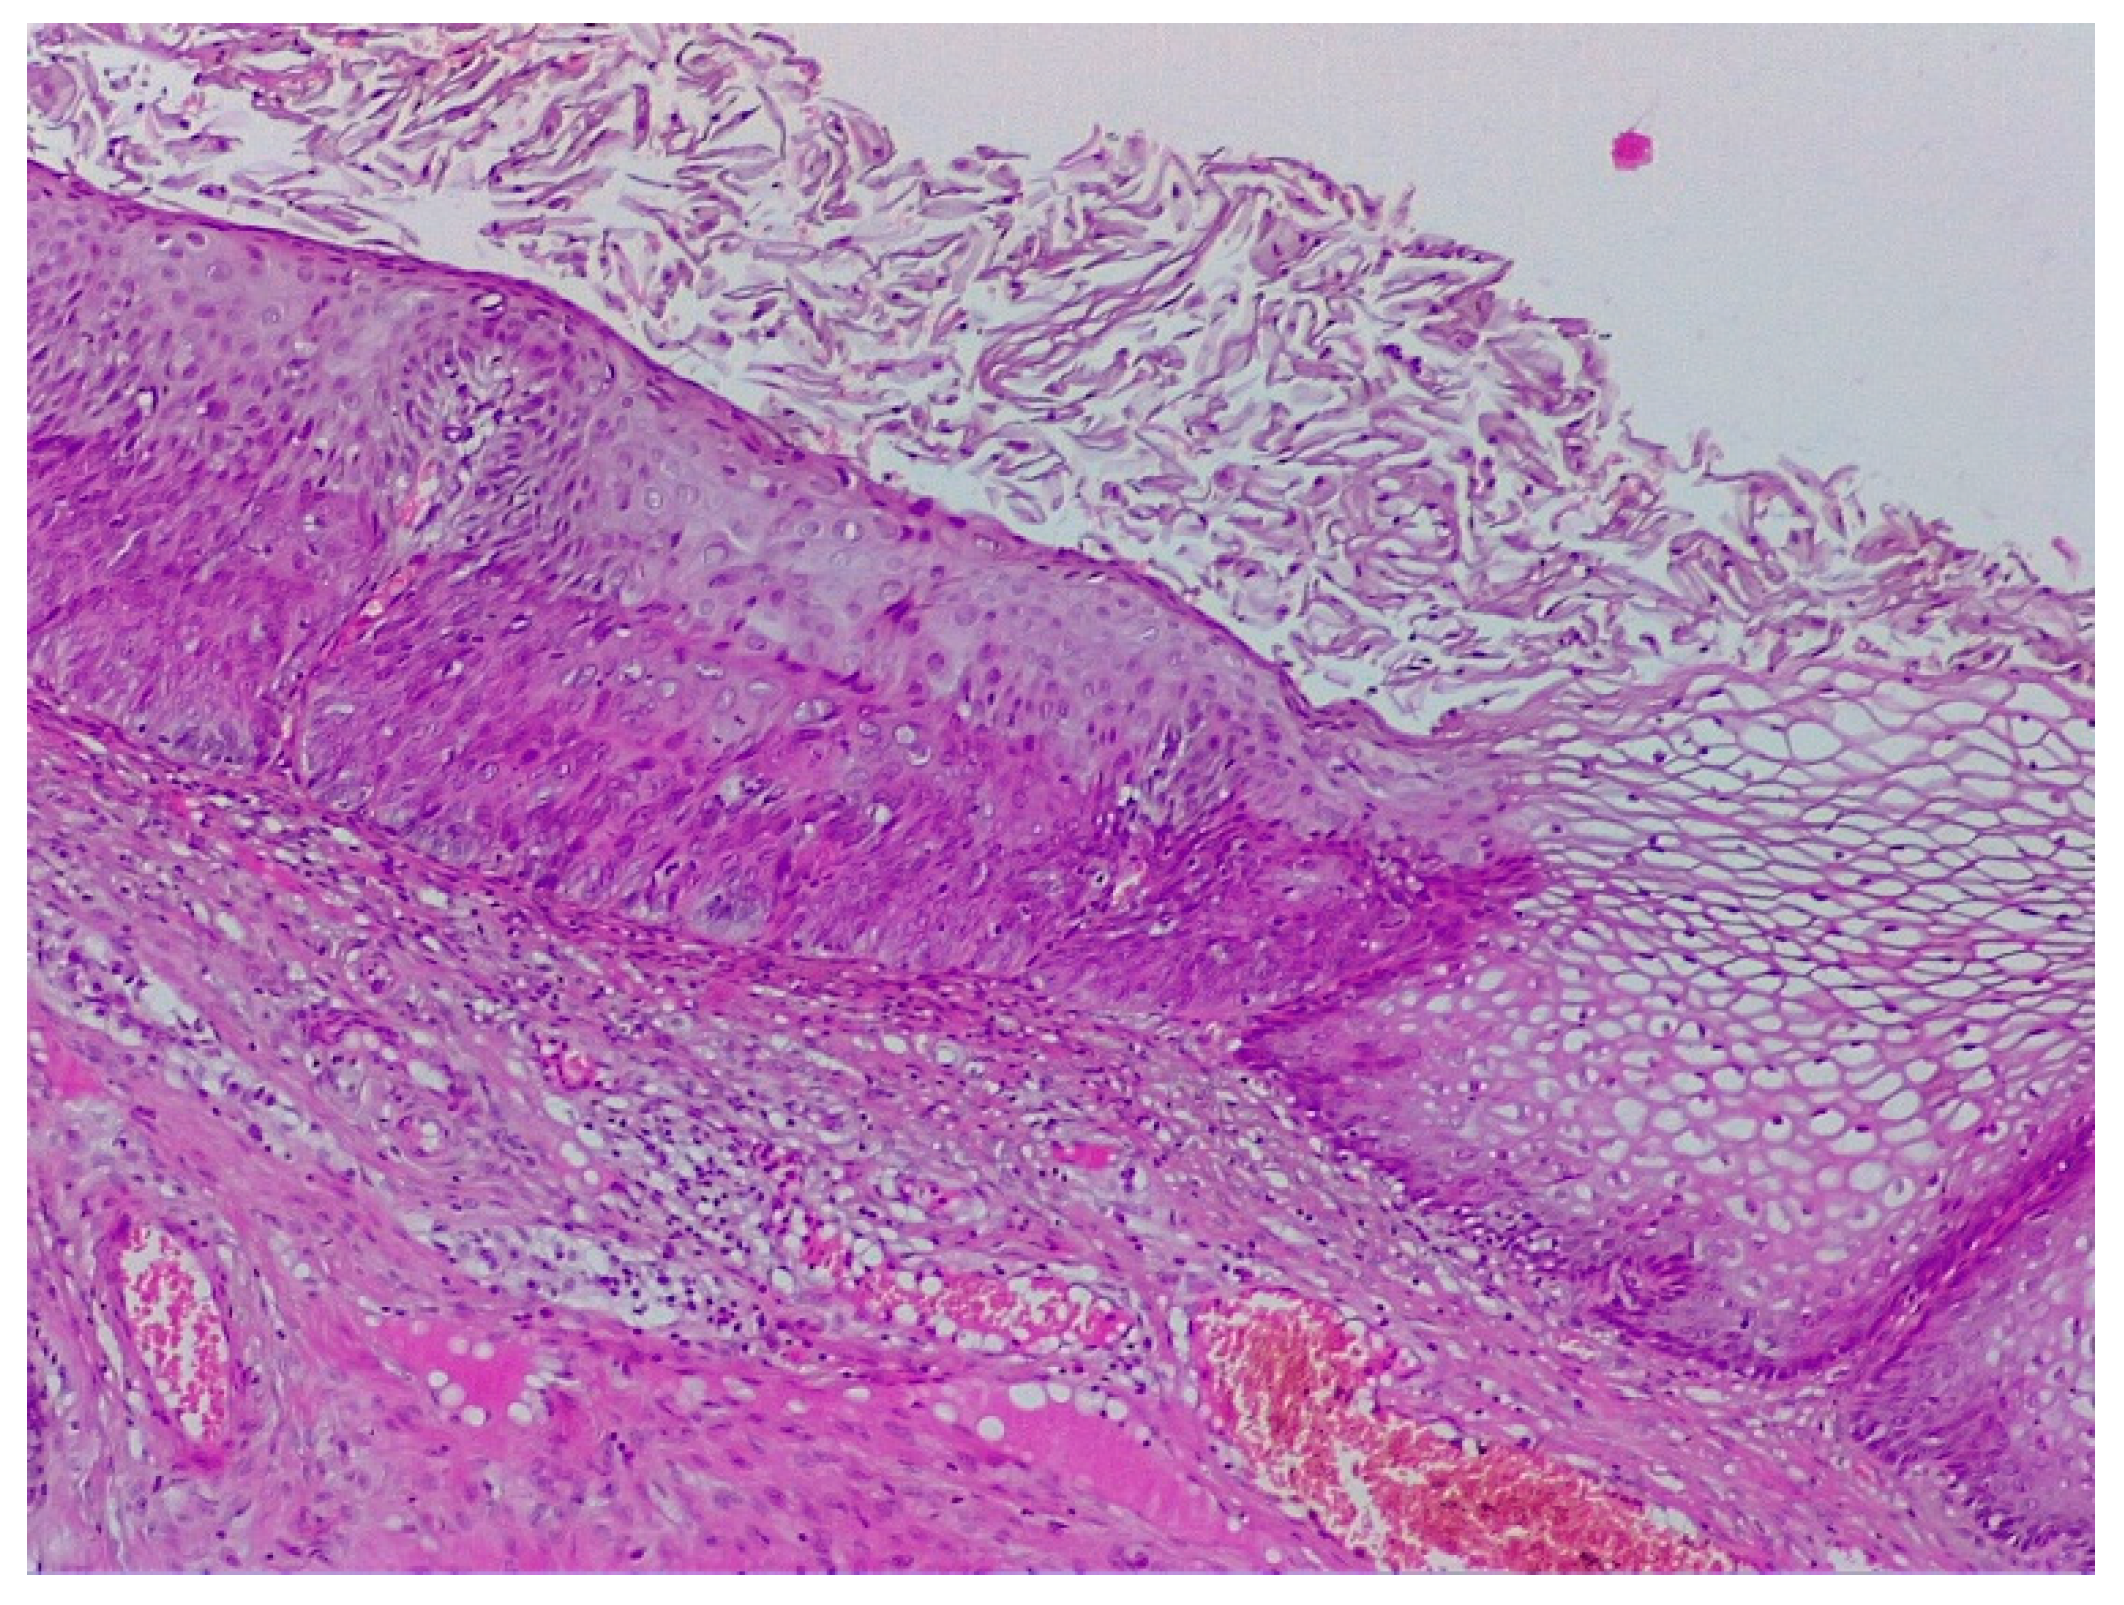

2.2. Clinical Examination